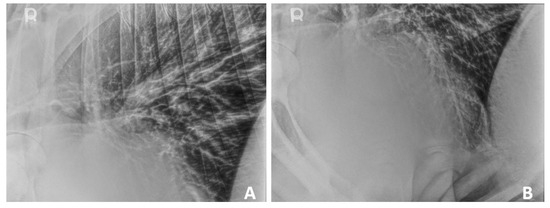

Thoracic radiographs (standing left-to-right laterals) were obtained (Figure 1A,B). Thoracic imaging demonstrated a diffuse broncho-interstitial pattern throughout the lung fields which raised the suspicion for chronic bronchitis or diffuse bronchopneumonia. There was also a focal alveolar pattern caudoventral to the cardiac silhouette, which raised suspicion for mild aspiration pneumonia or a localized exacerbation of bronchopneumonia. There was no evidence of thoracic lymphadenopathy or pleural effusion.

Figure 1. Standing thoracic radiography of a 2-year-old Aberdeen Angus with double-outlet right ventricular malformation. (A): Diffuse broncho-interstitial pattern throughout the lungs. (B): Diffuse broncho-interstitial pattern throughout the lungs, with a focal alveolar pattern caudoventrally to the apex of the heart.